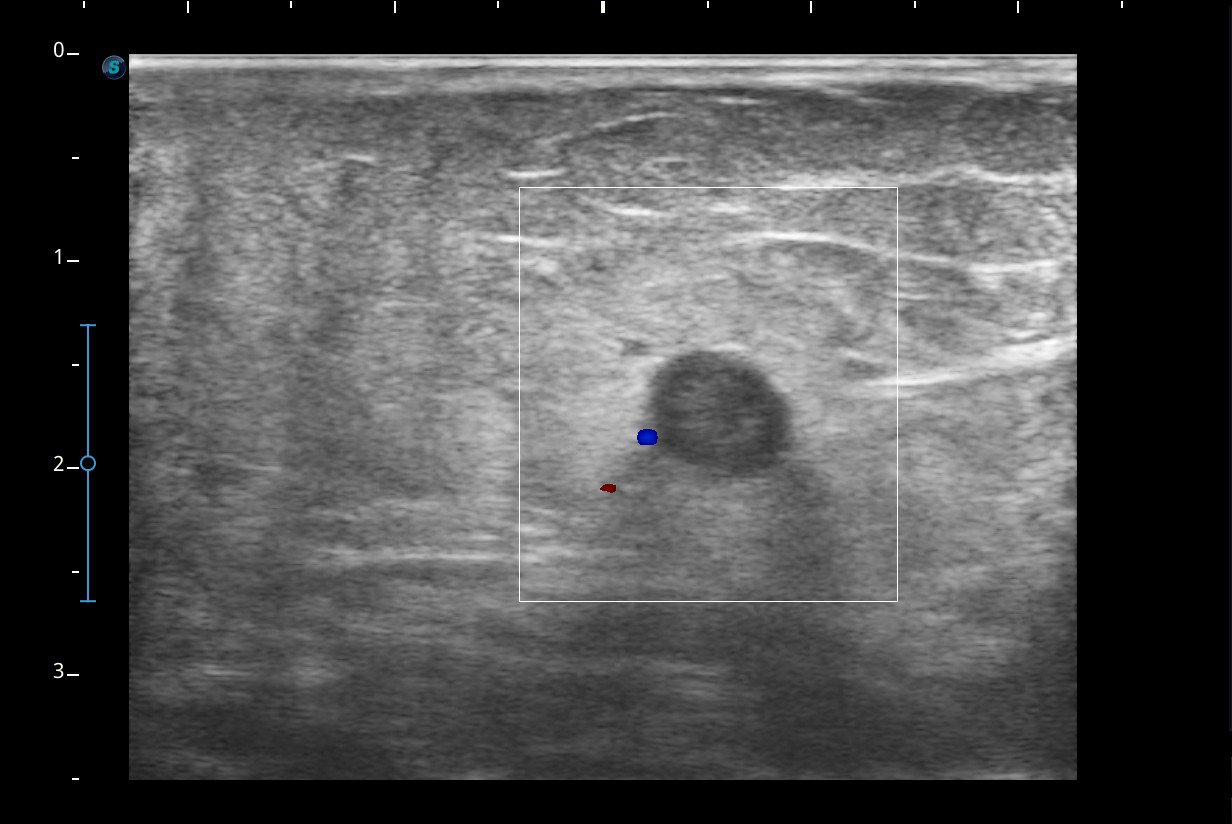

Se visualiza congestión del tejido subcutáneo del brazo y ocupación de la luz de la vena basílica del brazo por un trombo.

Diagnóstico: trombosis venosa de la vena basílica del brazo derecho. Concordancia con el hospital en el segundo tiempo que acude la paciente.

Se remitió a urgencias pero le realizan solamente radiografía del brazo y acude de nuevo a consulta. Nos ponemos en contacto con el SUH y realizan ecografía Doppler.